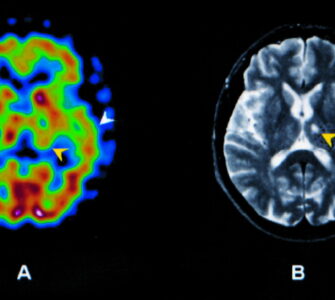

Brain Single Photon Emission Computed Tomography (SPECT) is a sophisticated imaging method that utilizes radioactive tracers to examine and visualize brain function. This nuclear medicine technique allows health...